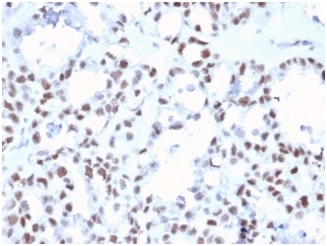

IHC staining of FFPE human ovarian carcinoma tissue with MLH1 antibody (clone MLH1/6467). HIER: boil tissue sections in pH 9 10mM Tris with 1mM EDTA for 20 min and allow to cool before testing.